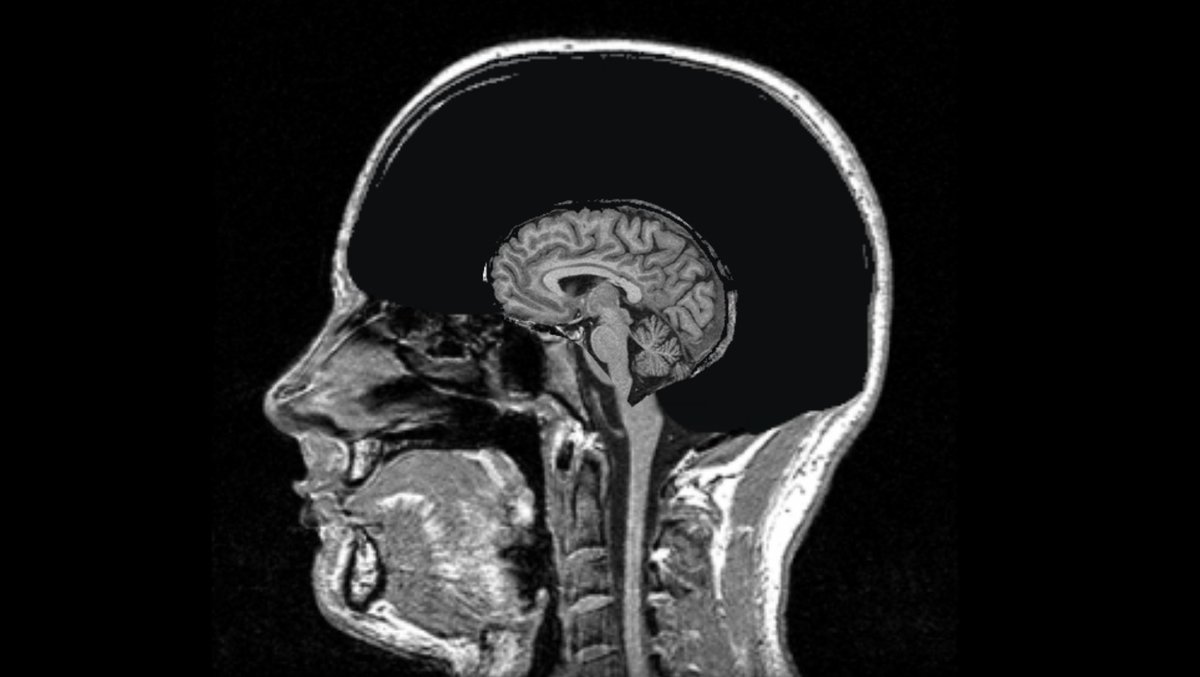

In Singapore, Rahul Gandhi came up with the idea of connecting all MRI (Magnetic Resonance Imaging) machines or scanners, and since then the internet is trying to decipher what exactly he meant and how is that going to help the humanity.

Rahul Gandhi had said that the entire healthcare sector on the planet would be transformed if all the MRIs were connected.